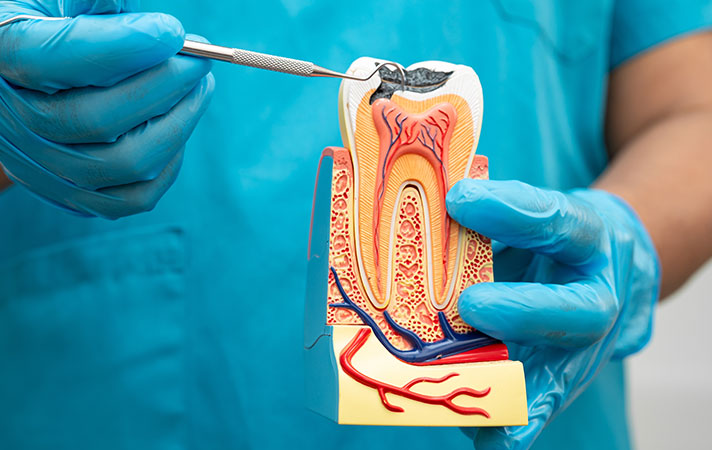

Teknoloji ve Estetiğin

Buluştuğu Nokta

Kliniğimizde en son diş hekimliği teknolojilerini kullanarak, hastalarımıza ağrısız ve konforlu bir tedavi süreci sunuyoruz

Sterilizasyon standartlarımız en üst seviyededir. Uzman hekim kadromuz, her hastamızın ihtiyacına özel tedavi planları oluşturarak, uzun ömürlü ve estetik sonuçlar hedefler.